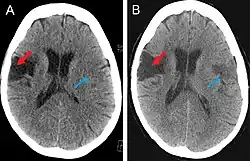

Frontal (coronal) section human brain. Lesions occurring in the highlighted regions are characteristic of Foix–Chavany–Marie syndrome.

There are two forms (also referred to as "classifications") of FCMS; bilateral and unilateral. The bilateral form is most common (also referred to as the "classical form") and is caused by the formation of lesions on both sides of the anterior or posterior region of the operculum. In contrast, the unilateral form is rare and is caused by the formation of lesions on one side of the anterior or posterior region of the operculum.[1] Lesions located in the anterior regions of the operculum are associated with motor deficits and anarthria, a total absence of the ability to form speech or language. Lesions located in the posterior regions of the operculum are associated with parietal opercular functions.[2] The two classifications of FCMS were established based on the location of the lesion, stroke, and trauma affecting the brain. Classifying FCMS based solely upon lesions yields five specific subtypes of FCMS currently known to fall into the bilateral and unilateral categories:[1][3]